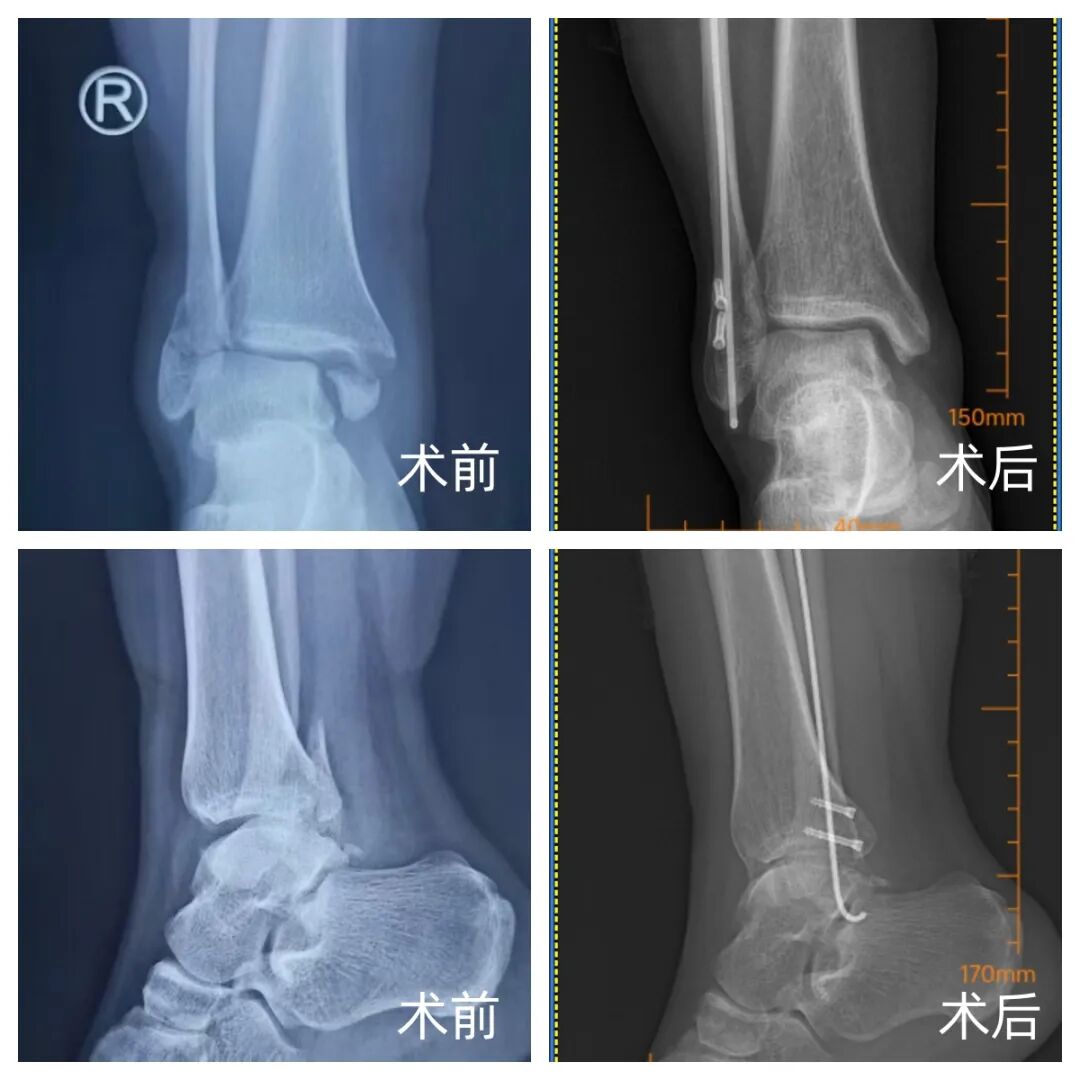

近年来,河南大学淮河医院创伤骨科郭建阔主任团队在临床开展弹性髓内针联合 Herbert 螺钉治疗外踝骨折的改良术式,截至目前已完成三十余例,取得了满意的临床效果。

针对上述问题,我院郭建阔主任团队采用弹性髓内针纵向髓内固定联合 Herbert 螺钉固定骨折断端的改良术式。该术式旨在最大限度恢复踝关节解剖结构与维持关节面平整,同时减少传统切开复位对软组织的干扰,为外踝骨折的手术固定提供了一种新的选择。

弹性髓内钉属于中心性内固定器械,其直径较细,术中无需扩髓,配合 Herbert 螺钉对骨折断端进行固定,有助于防止骨折旋转和成角移位,更好地稳定骨折断端,缓解局部疼痛,促进骨折愈合,并有利于术后踝关节活动度的恢复。由于该术式对皮肤软组织破坏较小,尤其对于开放性或闭合性软组织损伤明显的不稳定型踝关节骨折脱位,显示出良好的临床应用前景。